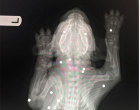

Röntgen felvételeket is készítettek róla. Ekkor valami szörnyű dolgot fedeztek fel az orvosok. Ebben a kis testben összesen 18 sörétes puskából származó golyót találtak.

Luckynak szerencséje volt, mert egyik golyó sem érte a csontjait, sem létfontosságú szerveket.

Mivel a kutya nagyon fiatal volt, még nem tudták elaltatni ezért nem tudták kioperálni a golyókat. Meg kellett várni amíg a kutyus kicsit idősebb lesz, hogy kibírja majd az altatást.